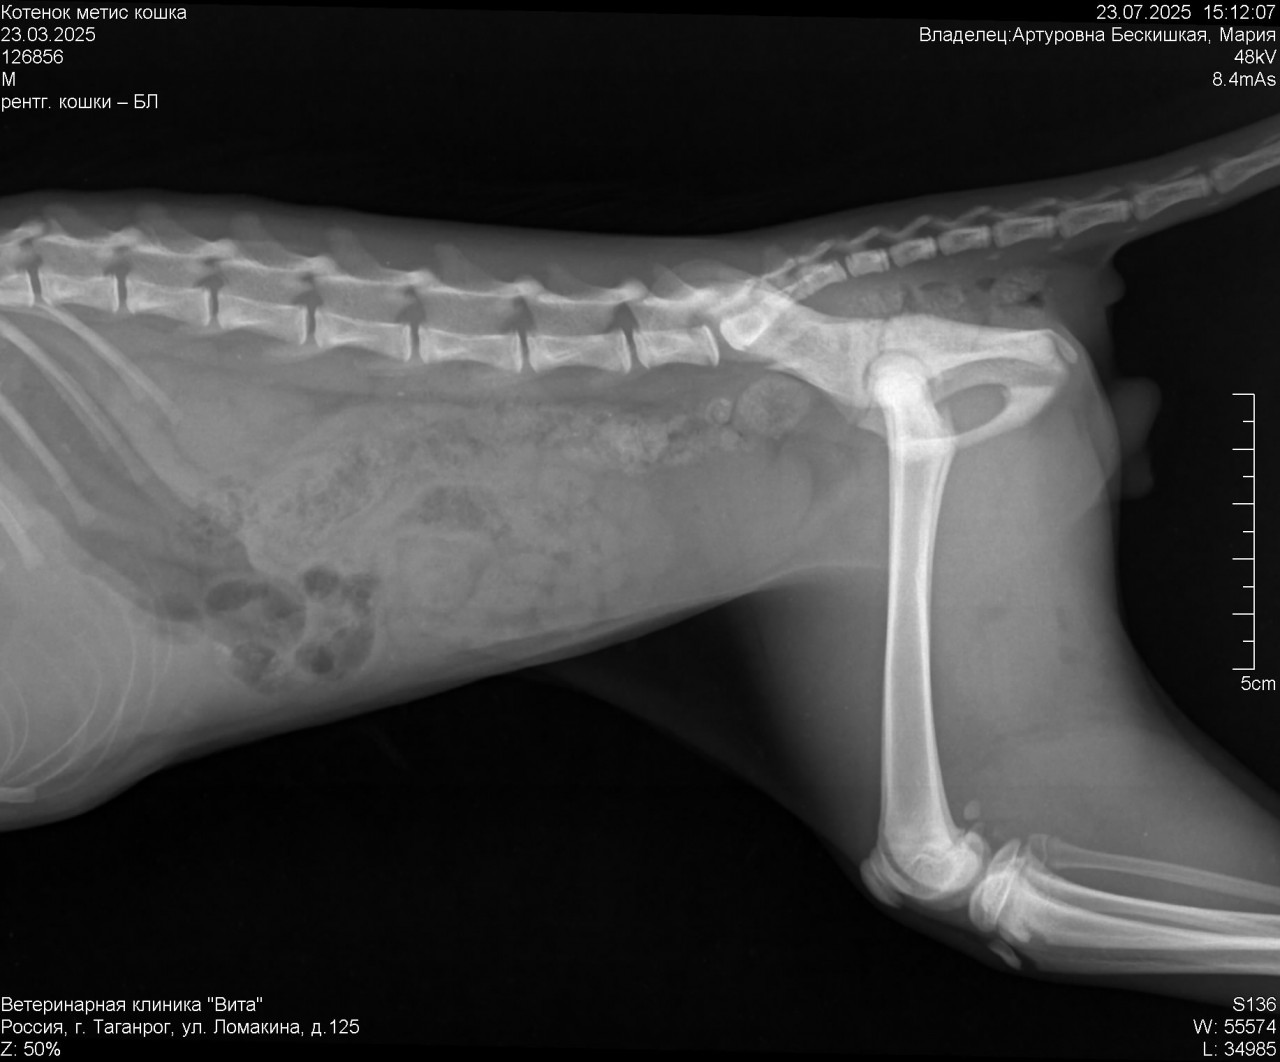

добрый день подобрали котенка упал с 12 этажа ,после объявились хозяева котенок оказался им не нужен . Вчера обнаружили перелом таза . Котенок уже кушает ,после обезбола стал сам мочится ,но по большому еще не ходил .

Действительно ли если котенок сам будет ходит в туалет ему не нужна операция? Не вызовет ли это проблем в будущем ? Снимок прикрепила

Здравствуйте. По рентгену у котёнка действительно отмечается перелом таза, но без выраженного смещения, которое угрожало бы жизненно важным функциям. Если он уже самостоятельно мочится это хороший признак. Дальнейшая тактика зависит от способности к дефекации и если в течение 3-4 дней котёнок начнёт ходить по большому и не будет признаков непроходимости, операция может и не понадобиться. Важно контролировать общее состояние, аппетит и живот (чтобы не появилось вздутие или болезненность).

Здравствуйте. Тактика ожидания в течение нескольких дней оправдана, особенно при стабильном состоянии и отсутствии сильного смещения костей. Основная угроза при переломах таза у котят  это нарушение работы кишечника и мочевого пузыря из-за сдавления или повреждения нервов. Если котёнок начнёт самостоятельно опорожнять кишечник и мочевой пузырь, то вероятнее всего операция не потребуется. Но в дальнейшем важно будет следить за походкой, положением таза и возможно сделать контрольный снимок. Реабилитация это покой, мягкая подстилка и при необходимости слабительные средства по назначению врача.